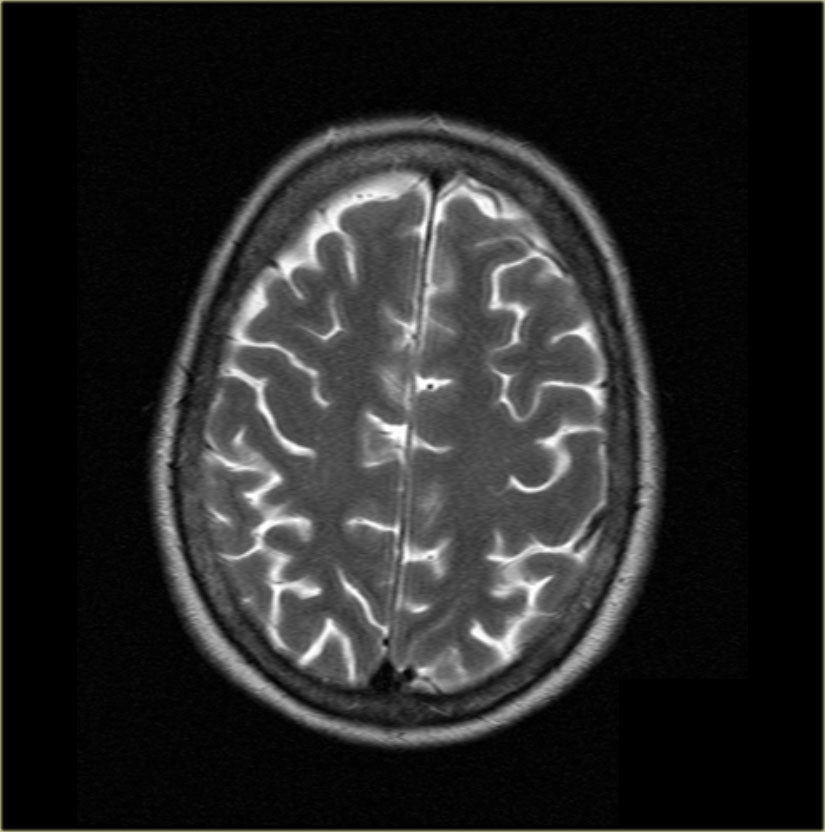

The head (1) is located in front of the mesencephalon, the body (2) can be found at the level of the mesencephalon and the tail (3) is posterior to the mesencephalon. To easily recognize the different portions of the hippocampus, we can use the mesencephalon (4). 1 = hippocampal head, 2 = hippocampal body, 3 = hippocampal tail, 4 = mesencephalon, 5 = amygdala, 6 = hippocampal digitations, 7 = temporal horn of the lateral ventricle, 8 = uncal recess of the lateral ventricle, 9 = splenium of the corpus callosum, 10 = subsplenial gyri, 11 = crura of the fornices. The hippocampal body is shown in detail in Fig. Zoomed-in 3-T coronal T2-weighted images at the level of the hippocampal head ( c) and the hippocampal tail ( d).